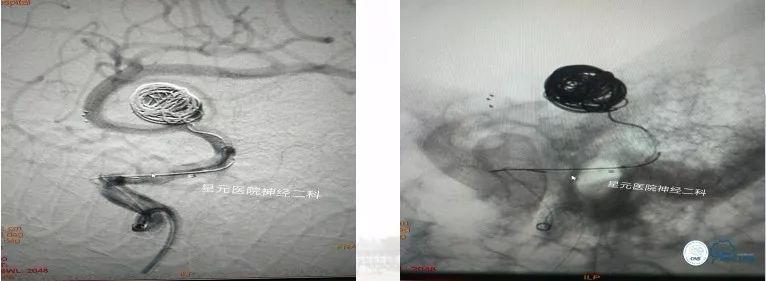

方案二:双支架辅助弹簧圈栓塞技术

➤双导管、双支架同时释放,保证M2段主干及瘤体所发出的眶额支通畅。

➤通过微导管A回收支架。将微导管A缓慢退至大脑中动脉M1段(中部),在0.014微导丝的导引下进行超选M2段主干,将微导管A头端对应瘤体9点钟方向,后通过微导管A将支架缓慢半释放到预定位置,保证支架尾端至于大脑中动脉M1段远端。

➤根据需要进行微导管B的头端蒸汽塑形,在微导丝的导引下将微导管B缓慢送至瘤腔内,进行侧枝开口的超选。多次尝试、反复超选,因侧枝开口与瘤体成角太锐而超选失败,随之放弃该方案。